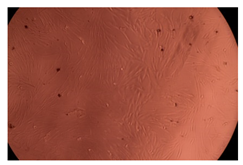

The results of the cytotoxicity assay, given in Figure 5, indicate that the tested PMs at all three established concentrations (10, 50, and 100 µg/mL) did not show cytotoxic effects on fibroblast cells at either 24 or 48 h after incubation. The percentages of cell viability were high, over 90%, in cells that were exposed to a concentration of 10 µg/mL for 24 h for all tested materials. Even at 48 h after incubation, the percentage of cell viability was as high as 90.4% in cells exposed to a concentration of 10 µg/mL for the Cop B sample. For both drug-loaded PMs, the cell viability decreased slightly at all tested concentrations. It also appears that the Dorzolamide-loaded PMs have slightly lower cell viability as compared to IMC-loaded PMs. Micrographs of the fibroblast cells after incubation times of 24 and 48 h are provided in Table 2.

Table 2.

Micrographs of fibroblast cells after 24 and 48 h incubation times, respectively.

As the cell viability values are all over 80%, the results indicate that the PMs, at the established concentrations, can be used successfully for in vivo biomedical applications.